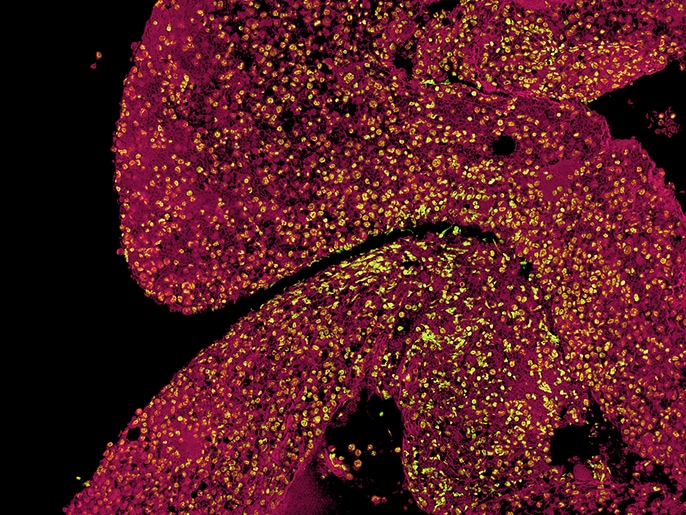

Norbert Gattermann und seine wissenschaftlichen Mitarbeiter*innen forschen zu Protein-Interaktionen an der inneren Mitochondrien-Membran und in der Matrix, um herauszufinden, warum das Eisen und das Porphyrin nicht richtig zusammenkommen. Mit dem Fluoreszenzmikroskop BZ werden Membrankomplexe auf strukturelle Anomalien untersucht, indem Protein-Protein-Interaktionen mit dem Proximity Ligation Assay (PLA) als Fluoreszenzsignale sichtbar gemacht werden. Die Sectioning-Funktion ermöglicht klare Aufnahmen ohne Fluoreszenzunschärfe. Es werden nur die Signale aus den fokussierten Ebenen extrahiert und daraus eine tiefenscharfe Aufnahme erzeugt. Die untersuchten Protein-Interaktionen betreffen die Ferrochelatase und ihre, zum Teil nur temporären, Interaktionspartner im „mitochondrial heme metabolism complex“.

Die sideroblastische Anämie ist eine Sonderform des MDS. In den Vorläuferzellen der Erythropoese findet hier eine massive Eisenüberladung der Mitochondrien statt. Seit den 50er Jahren des letzten Jahrhunderts ist diese Fehlfunktion bekannt und bis heute mechanistisch nicht geklärt. Vor einigen Jahren wurden Spliceosom-Mutationen im SF3B1-Gen gefunden, die bei 75-80 % aller Patient*innen mit sideroblastischer Anämie vorkommen. Sie führen dazu, dass die Mitochondrien zwar Eisen aufnehmen, welches aber durch das Enzym Ferrochelatase nicht effizient in Protoporphyrin eingebaut wird und sich somit in der Mitochondrienmatrix anhäuft. Das hat zur Folge, dass viel zu wenig Häm-Synthese stattfindet. Ohne Häm signalisiert die Zelle, dass noch Eisen fehlt, was zu einer weiteren Überflutung der Mitochondrien mit Eisen führt. Hier oxidiert das überschüssige Eisen und schädigt die Mitochondrien.